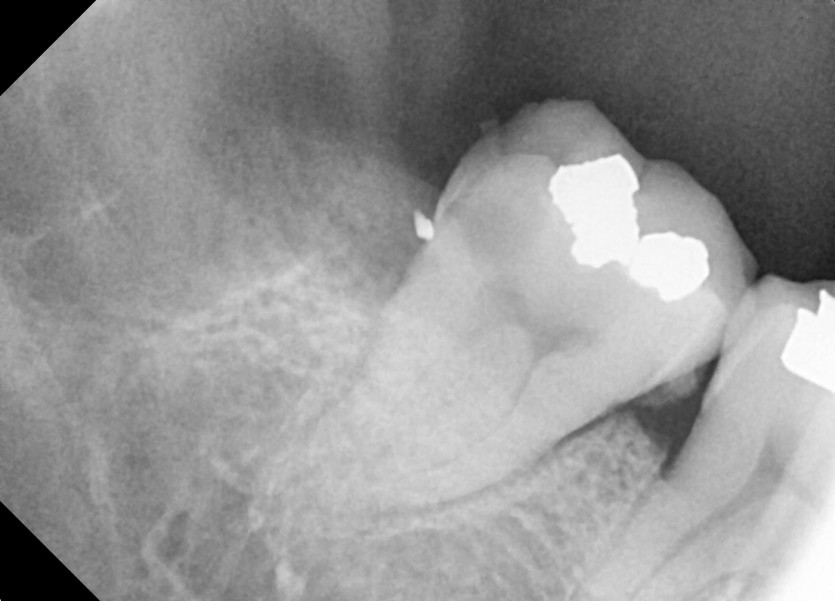

#48 사랑니 발치

구강 외과 전문의가 당일 발치했습니다.